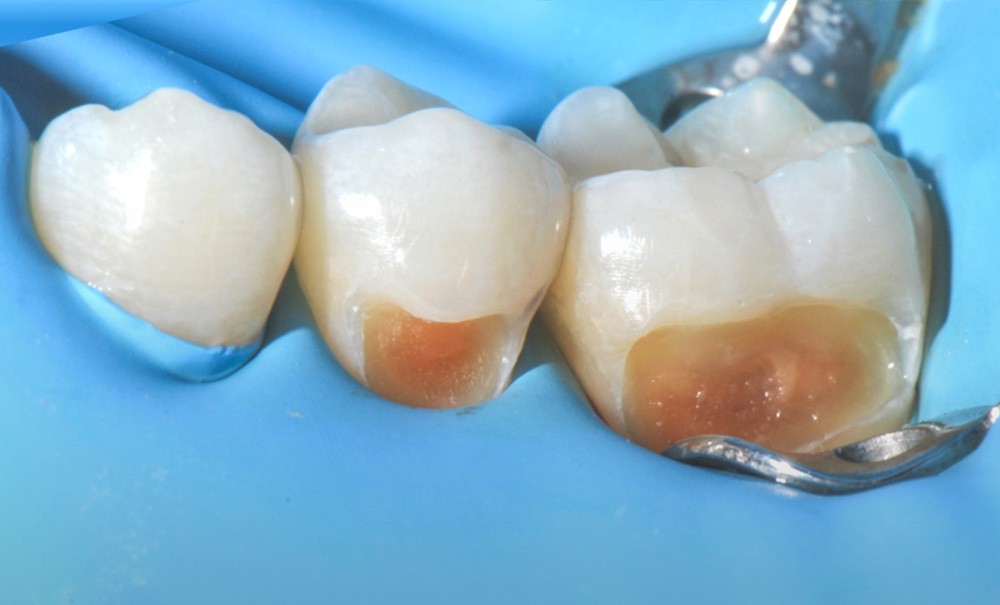

Le curetage sélectif s’inscrit dans une logique de préservation biologique maximale. Son principe s’appuie sur une cicatrisation naturelle plus que sur l’alternative produite par un biomatériau. La procédure consiste en l’élimination complète, en périphérie, de la dentine cliniquement altérée (dentine nécrosée, infectée et affectée) jusqu’à l’obtention d’un tissu dur et sain, mais en conservant volontairement une dentine affectée au niveau parapulpaire (fig. 5). L’objectif est de limiter l’agression mécanique directe de la pulpe et de favoriser ses mécanismes de défense, notamment la formation de dentine tertiaire, la dentine affectée jouant le rôle de matrice biologique de cicatrisation. Cette stratégie revient à contrôler la lésion dans un environnement…